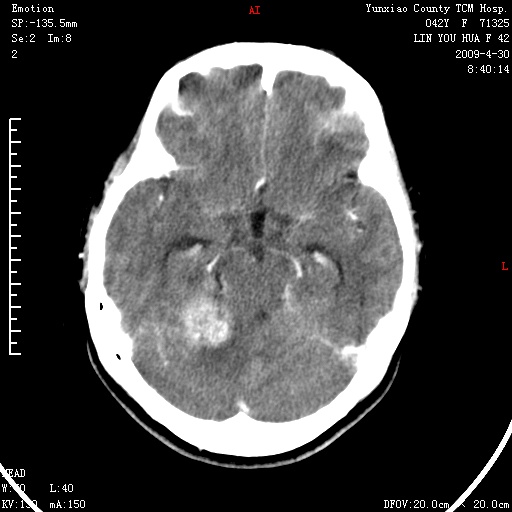

右侧桥小脑角区肿瘤,高密度囊变有显著强化,骨窗见内听道显著扩大,考虑听神经瘤可能性大

1)右侧听神经瘤。2)阻塞性脑积水。